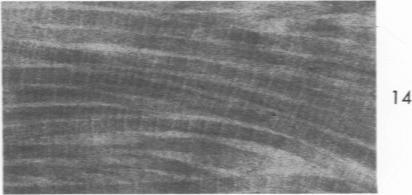

Thickening of arterial intima in rat cardiac allografts. A light and electron microscopic study.

Am J Pathol. 1971 Apr;63(1):69-84.